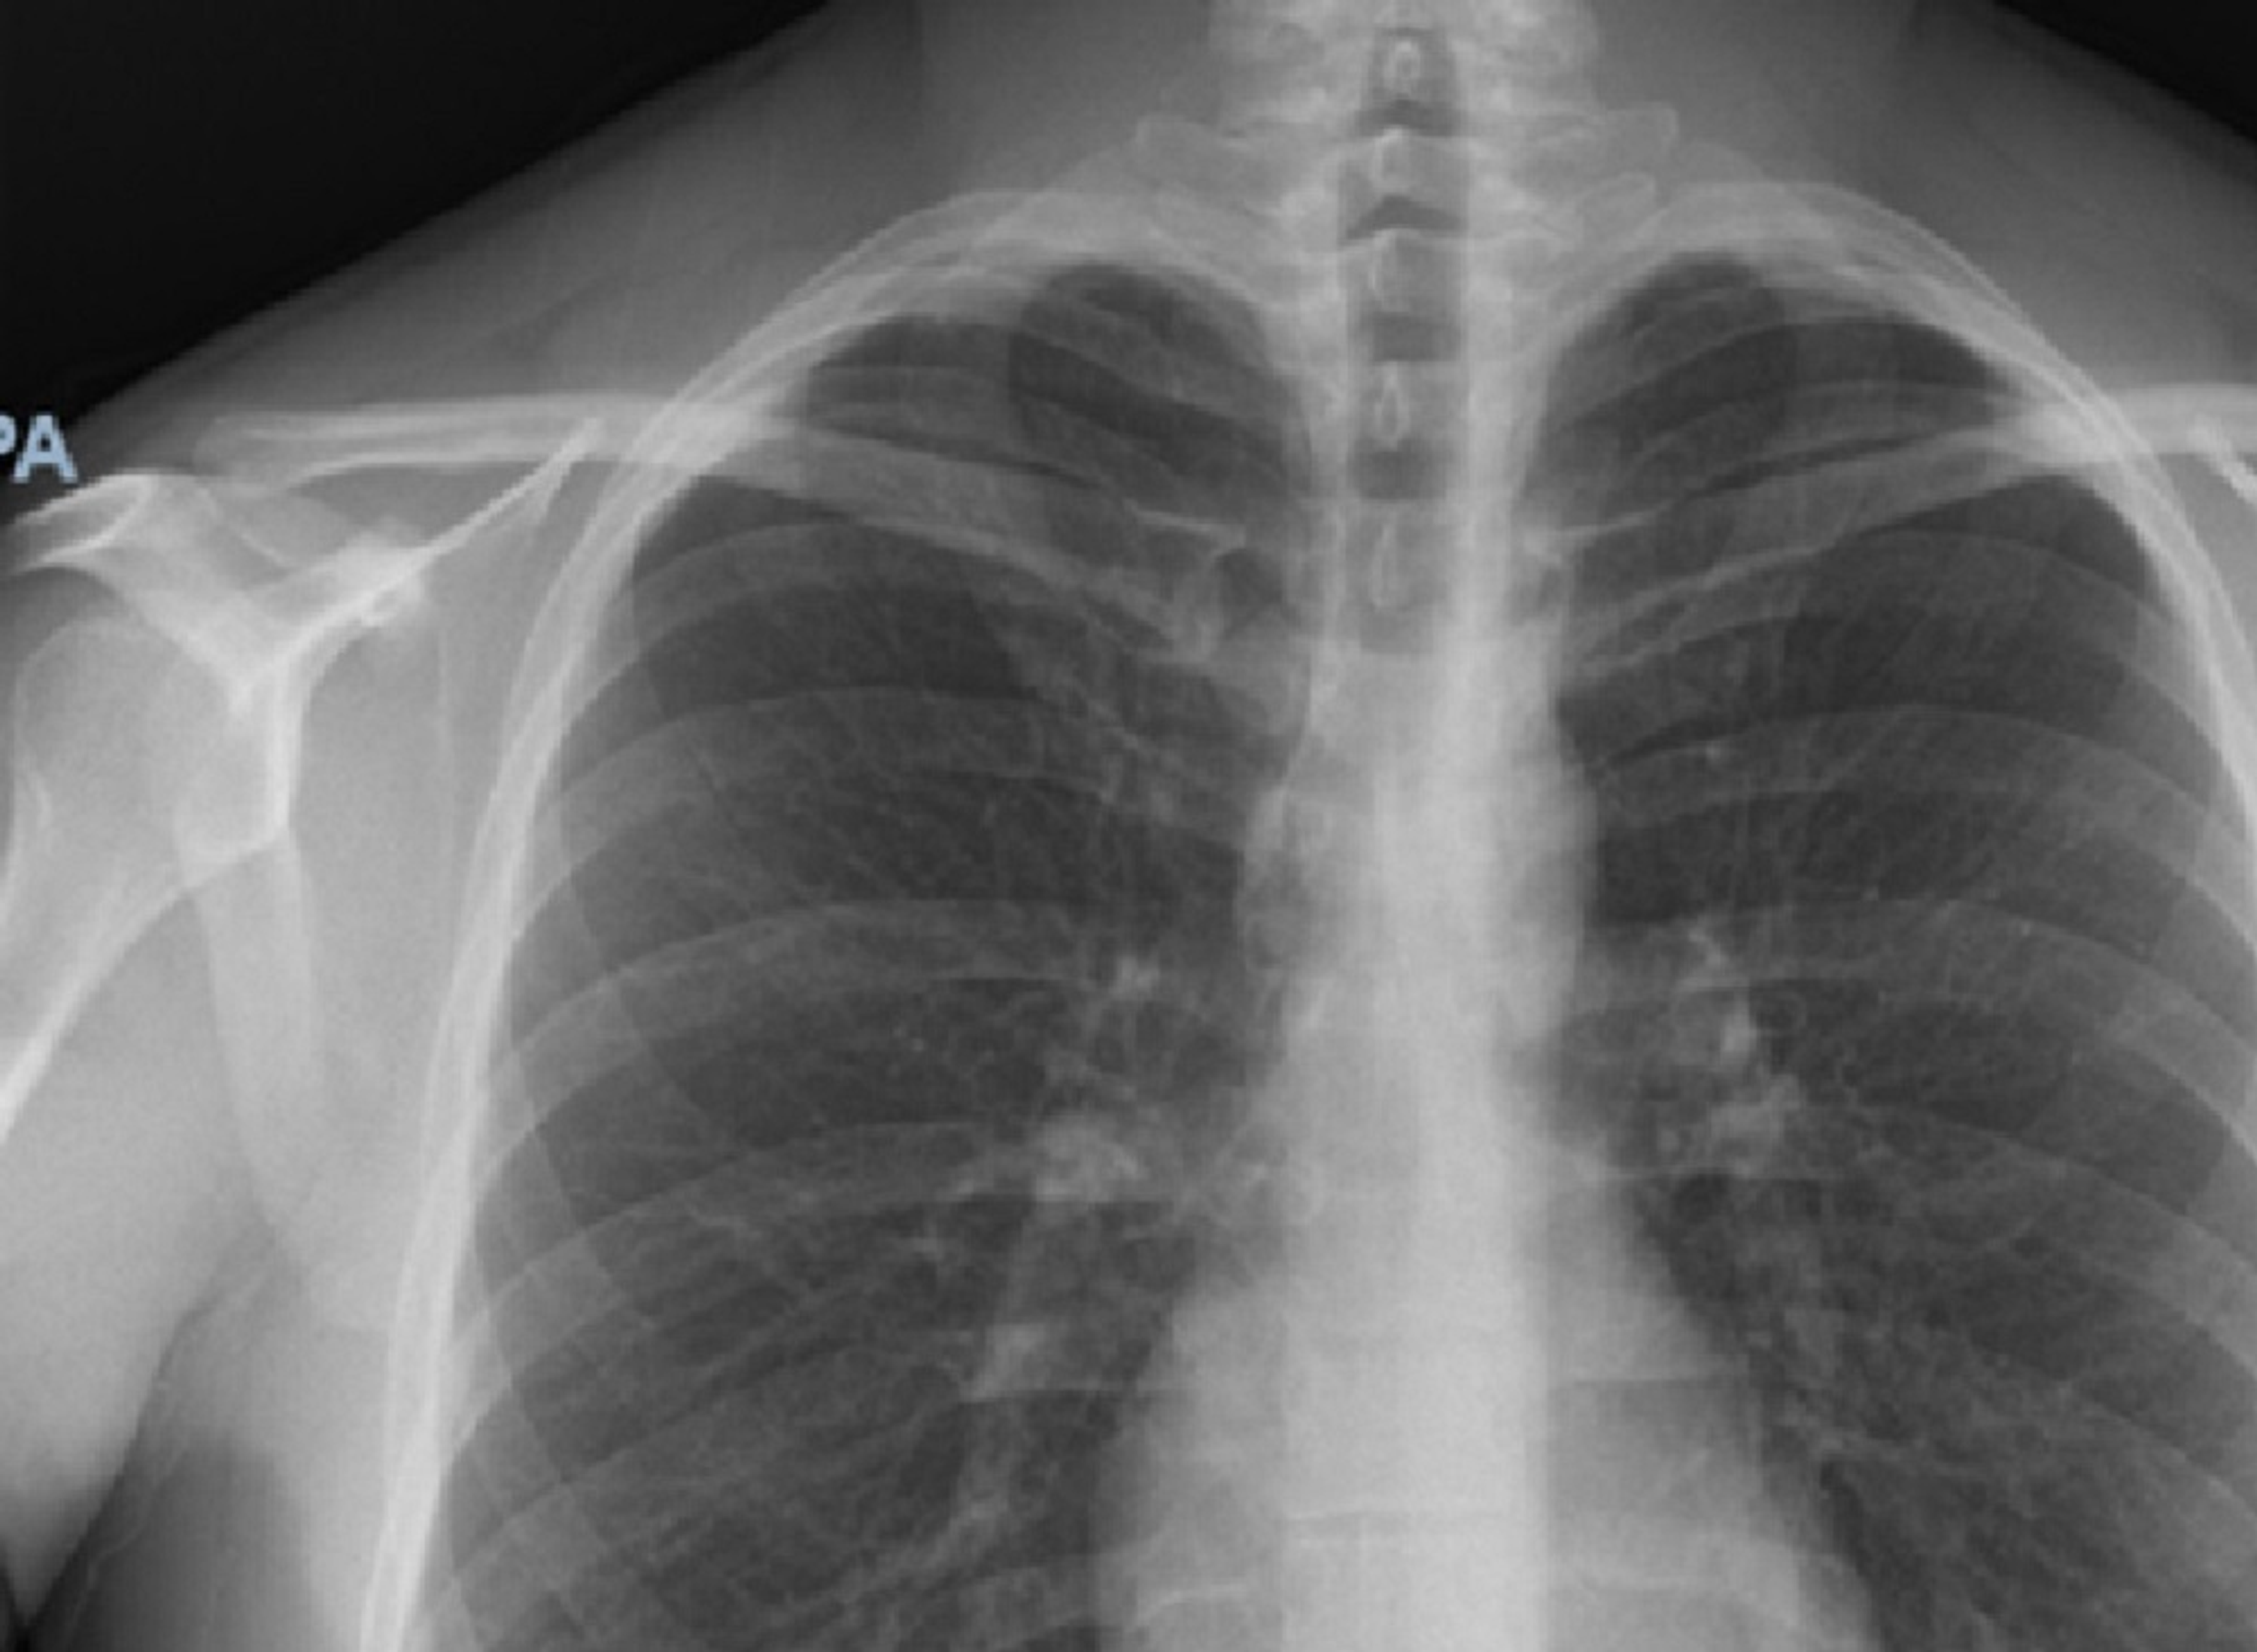

XRay Image of Healthy Chest Stock Image Image of myocarditis Can A Chest X-Ray Show Myocarditis a typical appearance of myocarditis on mri in the correct clinical setting may obviate biopsy. myocarditis is usually suspected based on the patient's story and physical exam. chest radiography is considered usually appropriate in the setting of chest pain in patients with low to intermediate probability. Will often be normal in myocarditis, but it may show features. Can A Chest X-Ray Show Myocarditis.

From www.dreamstime.com